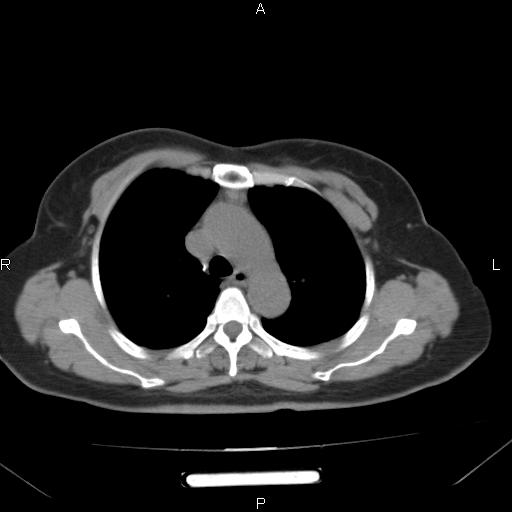

胸腺瘤

女、63Y 双眼睑下垂,早轻晚重。 胸腺瘤???

结果胸腺瘤